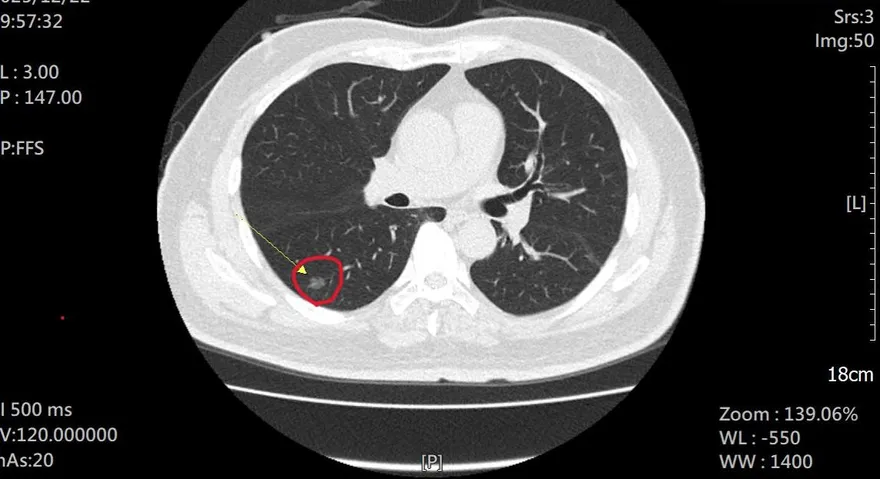

老菸槍為抱孫戒菸!檢查發現「1公分肺腺癌」撿回一命

肺腺癌

毛玻璃狀病變